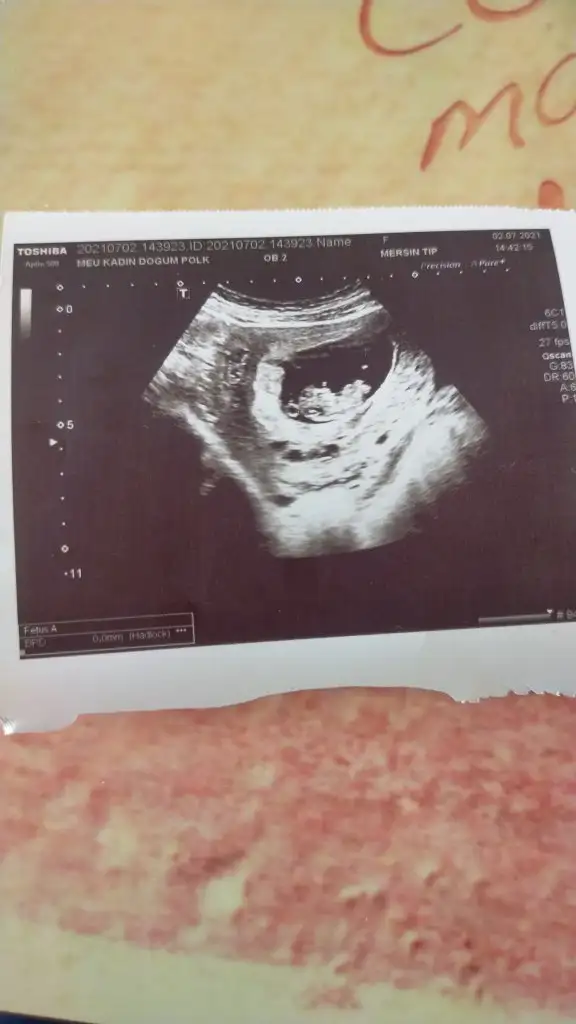

Bugün 10+2 yim kanama alanlarım var ama çok küçükmüş doktor birşey olacağını sanmıyorum dedi progestan hapa devam ediyorum bu görüntüde hala bebeğimi ayırt edemiyorum başı hangi tarafta ayakları nerde görebilen var mı

Başı solda canım, mersinde mi yaşıyorsun?